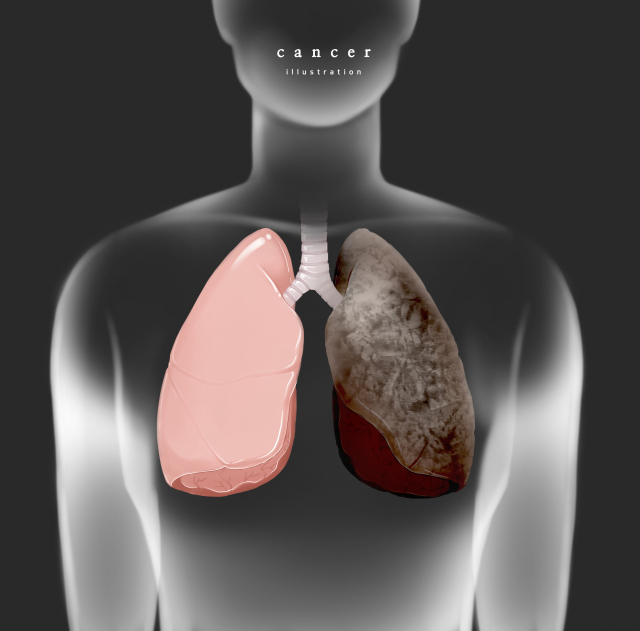

폐암 원인

폐암의 가장 중요한 위험인자는 흡연입니다. 폐암 사례의 약 70%는 흡연과 관련이 있으며 흡연자는 비흡연자보다 폐암 발병 위험이 10배 높습니다.

흡연 이외의 위험요인을 살펴보면, 간접흡연이나 석면 등에 계속 노출되면 10~35년의 잠복기를 거쳐 폐암이 발병하는 것으로 알려져 있습니다.

흥미롭게도 최근에는 폐암에 걸린 비흡연 여성의 수가 증가하고 있습니다. 간접흡연, 요리 스모그 및 실내 공기 오염이 증가의 큰 요인으로 보고 있습니다. 건강검진 활성화에 따른 폐암 발견율 증가도 폐암 발병률 증가의 원인으로 지목되고 있습니다.

미세먼지 역시 폐암 발병률을 높이는 1급 발암물질로 보고되고 있습니다.